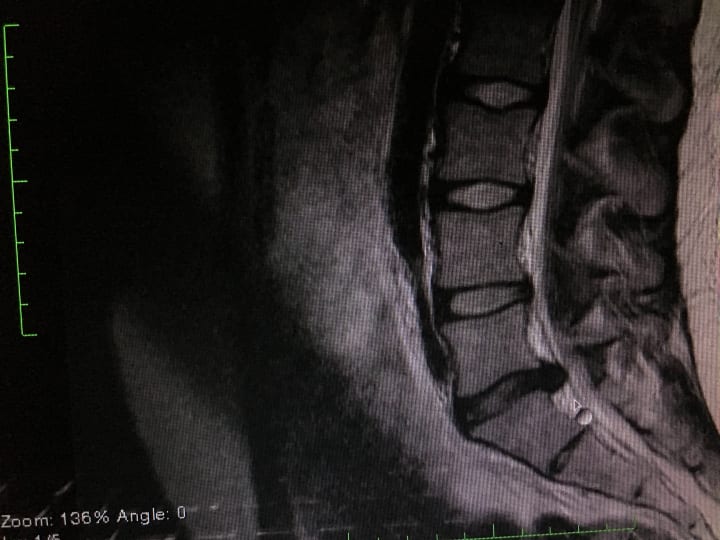

In 2016 I underwent a private surgery to bid adieu to the chronic nerve pain, and lower back pain that had haunted my life for far too long. My family and I were at our wits' end with hearing the word chronic, followed by the word pain. It was time to try a new avenue; one that was not offered by the cookie cutter approach of the Canadian healthcare system. It was time to stop using my no-gravity chair as a crutch, and to stop relying on everyone around me to pick up the thing that I had dropped on the floor (as much as I loved that). The possibility of being free from the imprisonment of back pain that I had grown familiar with was an absolute dream. Being a former rower, swimmer and twenty-three year old who had enjoyed movement, being active and being upright, I was beyond excited for the possibility of returning to the physical activities I loved.